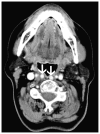

Cross-sectional imaging plays an important role in the evaluation of the retropharyngeal space (RPS) and the prevertebral space (PVS). Because of their deep location within the neck, lesions arising within these spaces are difficult, if not impossible, to evaluate on clinical examination. This article details the cross-sectional anatomy and imaging appearances of primary and secondary diseases involving the RPS and PVS, including metastasis and spread from adjacent spaces. The role of image-guided biopsy is also discussed.